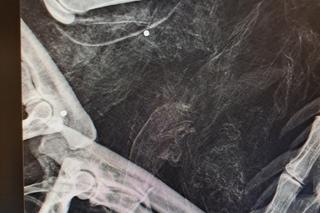

"Cleo, została znaleziona w okolicach Piasecznika (gm. Choszczno) w stanie rozkładu" - informują przyrodnicy. - "Po zbadaniu ciała w jej szczątkach zabezpieczono kilka śrucin".